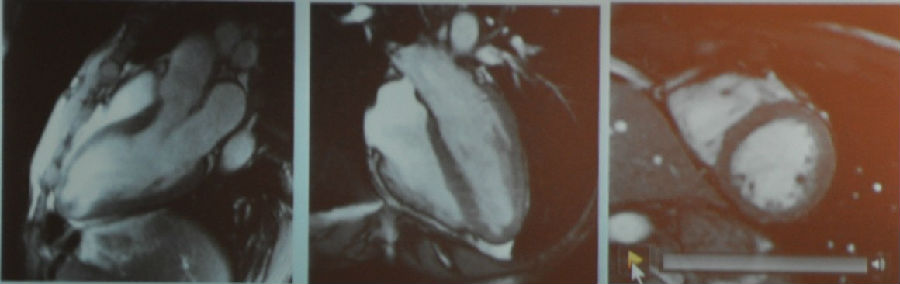

图2 MR电影成像

室间隔壁变薄,心尖部收缩功能不全,短轴观示前壁收缩功能不全。心尖部有异物。

图3 MR增强成像(从左到右依次为三腔心切面、四腔心切面、短轴切面)

从MR增强成像中可以看到,心脏上黑色的部分是正常心肌,而白色的部分为瘢痕组织。该图显示了心肌梗死的典型表现。通过增强我们可以看到心尖部的异物是一个血栓,这个在一般的心脏超声上是难以发现的,因为它非常小。我们还可以看到,实际上患者心梗的面积要比上面短轴观所示前壁收缩功能不全的程度严重得多。

那么这名患者的诊断就非常明确了,是缺血性心肌病。他很快被送往导管室行PCI治疗。3个月后患者再次来院行磁共振检查,其心脏收缩功能获得了显著的改善。